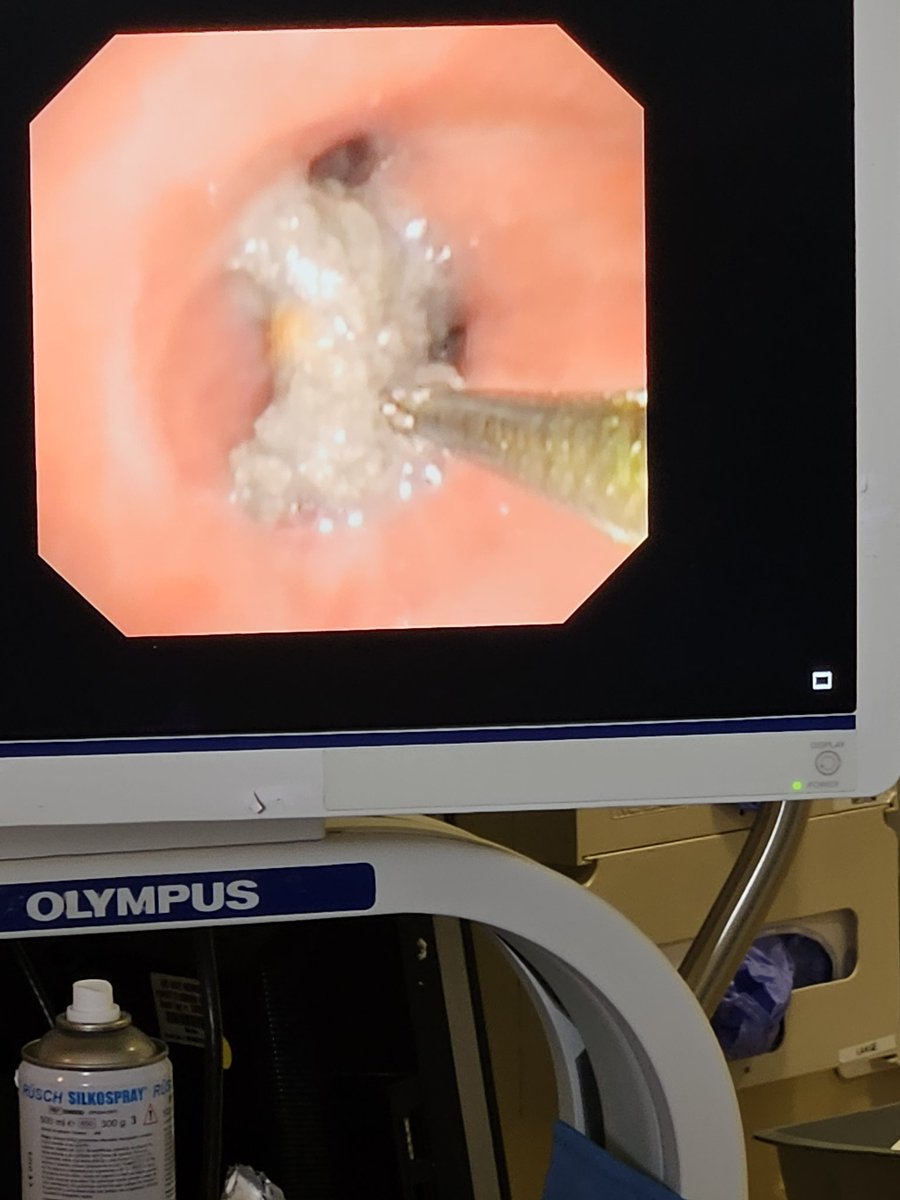

Just another day in the neuro icu! 🎣 Foreign body removal ( rock) with a flexible bronch! Extracted with a retrieval basket + tube exchange given its large diameter. #neurotrauma @HuimahnChoi @UTH_Neurocrit